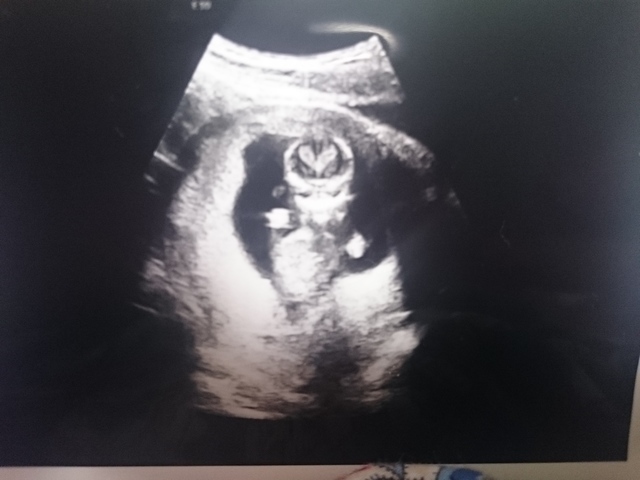

13週3日(13w3d・男の子)|りゃん0608 さん(35歳)

エコー写真撮影時のエピソード:

妊娠13週の頃、初めて人間らしい表情が写ったエコー写真を見て、めちゃめちゃカメラ目線!!のようでビックリしたのと同時に、かわいい!!って思ってしまいました!目が開いてるはずはないのにパッチリお目目のように見えてお気に入りのエコー写真です。出産が待ち遠しいです♪